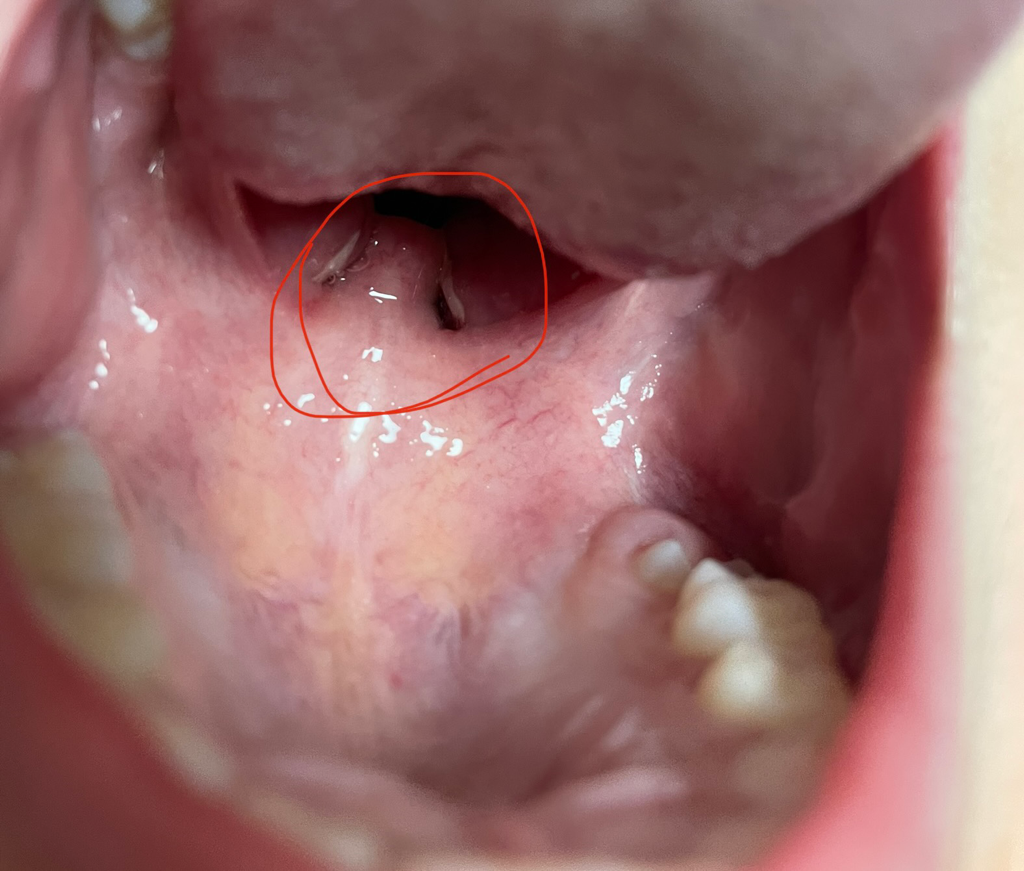

아이 편도에 하얗게..뭘까요?

아이 편도에 저렇게 하얗게 뭐가 붙어있는것처럼 생겼어여..ㅠㅠ저게 뭘까요?열도없고 목도 안아프다고하고 잘먹거든요 ㅠㅠ갑자기 생긴거라 걱정되네요.아 해보면 옆으로도 하얗게 퍼져있어요

• 안녕하세요. 서민석 의사입니다.

아프다고 하지 않으면 그냥 놔두셔도 됩니다. 편도 결석일 것 같습니다. 입에 냄새가 좀 나는 것 말고는 크게 불편하지 않을 겁니다.